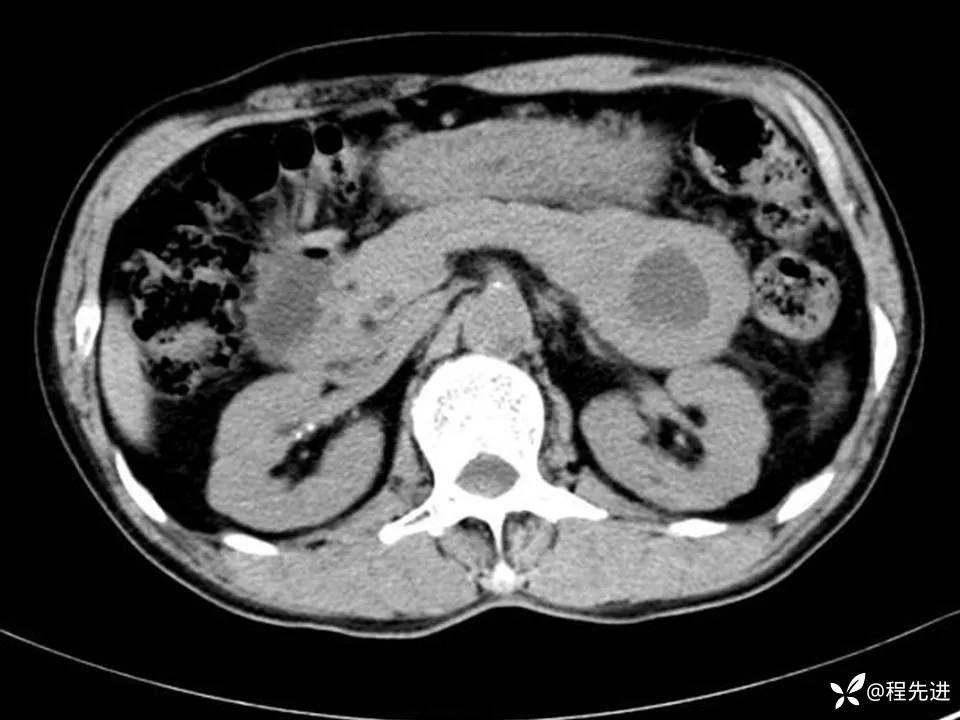

患者性别:男

患者年龄:61岁

简要病史:体检发现胰腺占位

实验室检查:(-)

CT平扫+增强:

胰腺癌 (88)